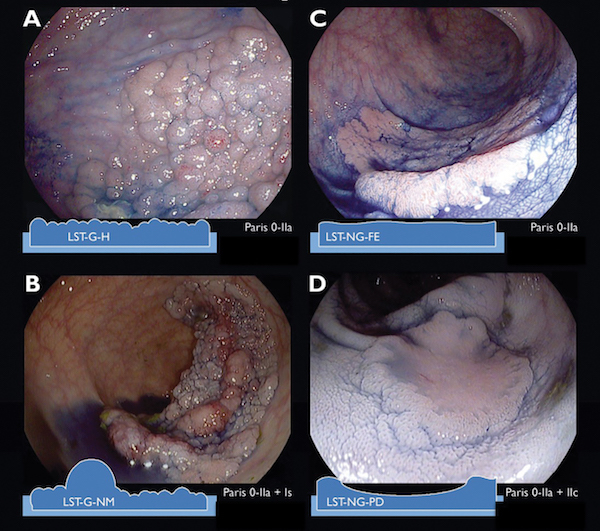

A 56-year-old man with no significant past medical history presented for screening colonoscopy. His examination was remarkable for a 1.8-cm laterally growing superficial area of irregular mucosa in the ascending colon that you suspect is a lateral spreading tumor (LST). What LST sub-classification [FIGURE] has the highest risk of submucosal invasive cancer?

A. Granular, homogenous

B. Granular, nonhomogenous

C. Nongranular, flat elevated

D. Nongranular, pseudodepressed

In one study of lateral spreading tumors (LSTs), submucosal invasion (SMI) was identified in 8.5% of cases and high-grade dysplasia in 36.7% of cases. Within this study, geographic region did not influence the SMI risk and nongranular LSTs were more frequently associated with SMI than granular LSTs: 11.7% vs. 5.9%. The prevalence of SMI in LSTs stratified by endoscopic LST subtype were: 31.6% in pseudodepressed nongranular LSTs, 10.5% in nodular mixed granular LSTs, 4.9% in flat elevated nongranular LSTs, and 0.5% in homogenous granular LSTs. Within that study, SMI was also more common in distal rather than proximal LSTs and the proportion of SMI increased with lesion size (10-19 mm, 4.6%; 20-29 mm, 9.2 %; ≥30 mm, 16.5%).